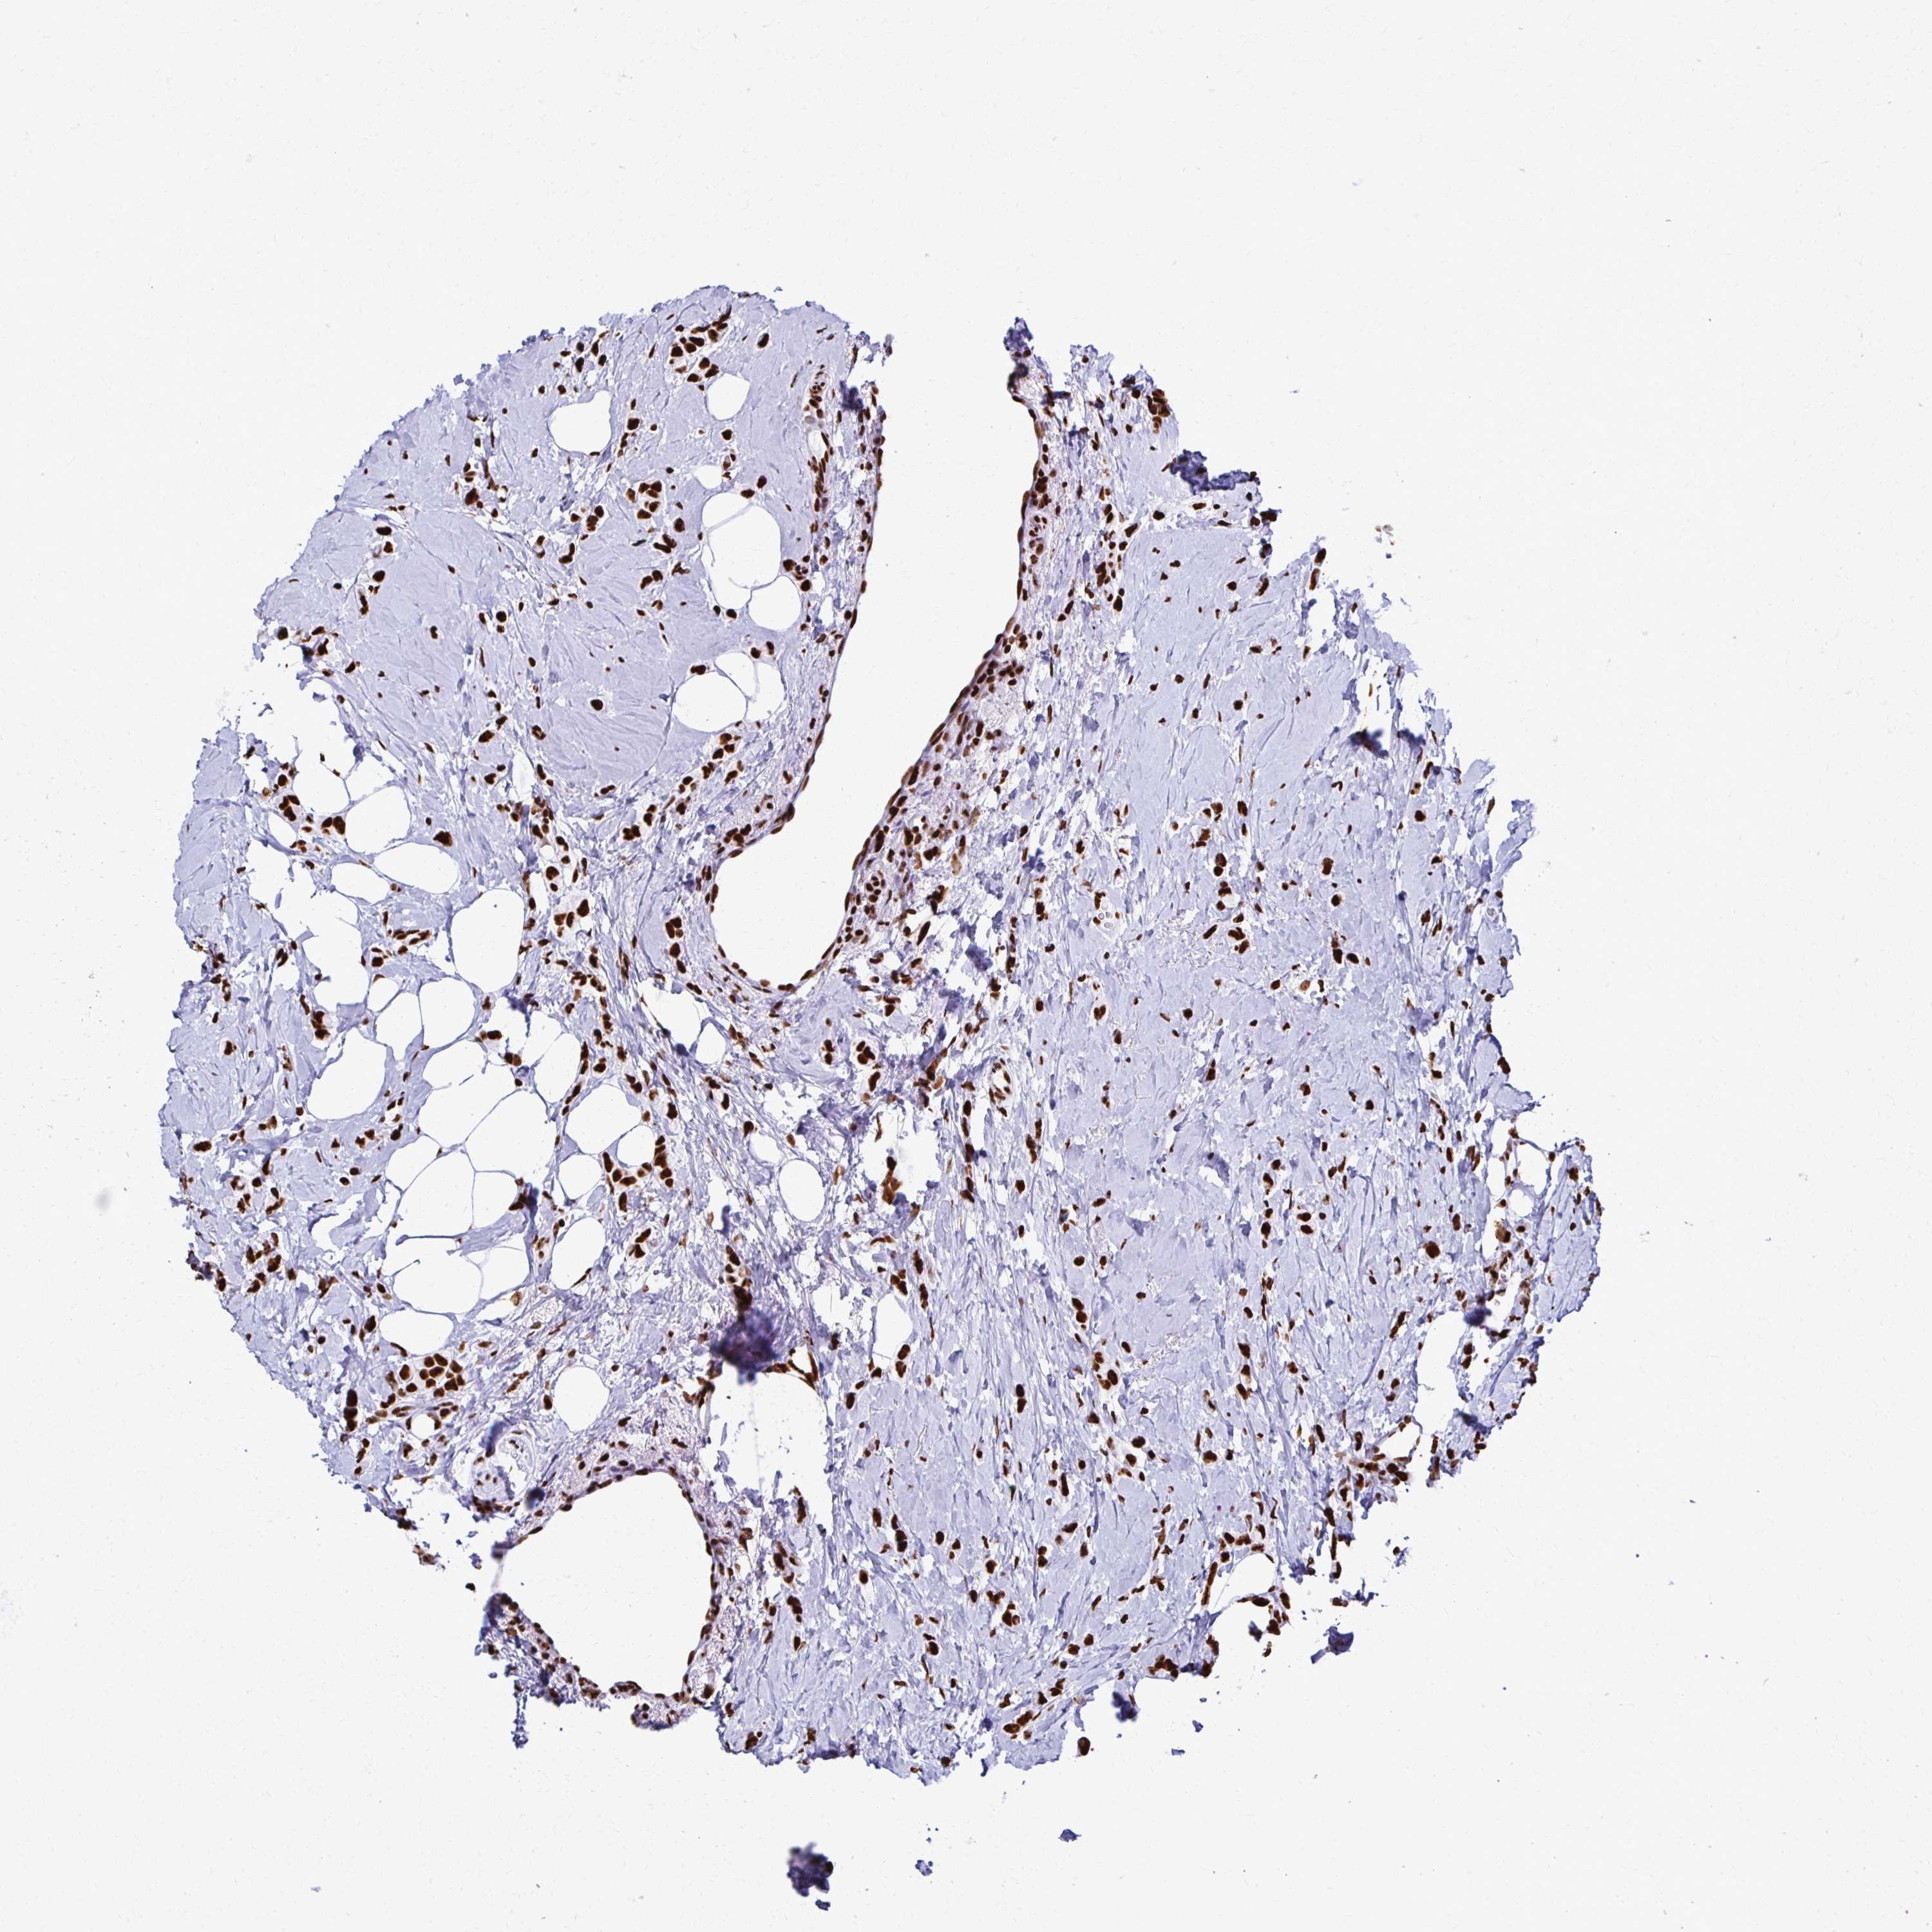

CANCER BREAST CANCER Show tissue menu

BRCA TCGA BRCA VALIDATION PROTEIN EXPRESSION